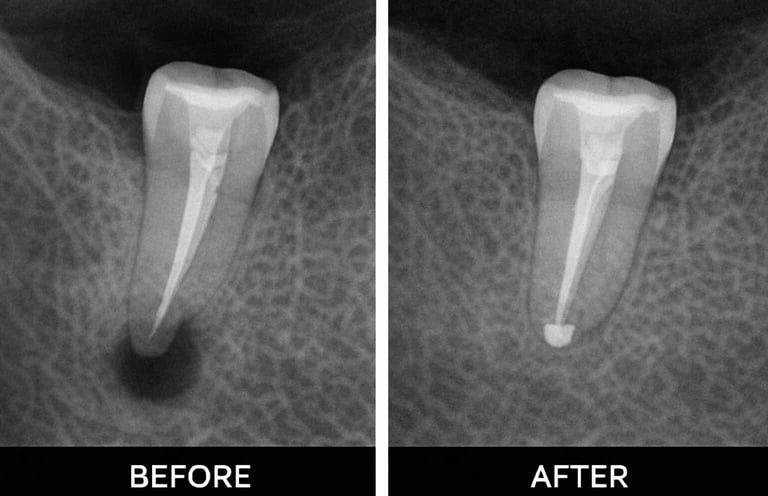

Examination & X-rays – determine the extent of infection or damage

Root canal treatment removes infected or damaged pulp from inside a tooth. The pulp contains nerves and blood vessels, and infection can cause pain, swelling, or abscesses. During the procedure, the dentist cleans out the infection, shapes the root canals, and fills them with a safe material. Finally, the tooth is restored with a crown or filling to protect it. Root canals prevent infection from spreading and help keep your natural tooth

Multi-Root Tooth

Molars often have 2–4 canals that need treatment.